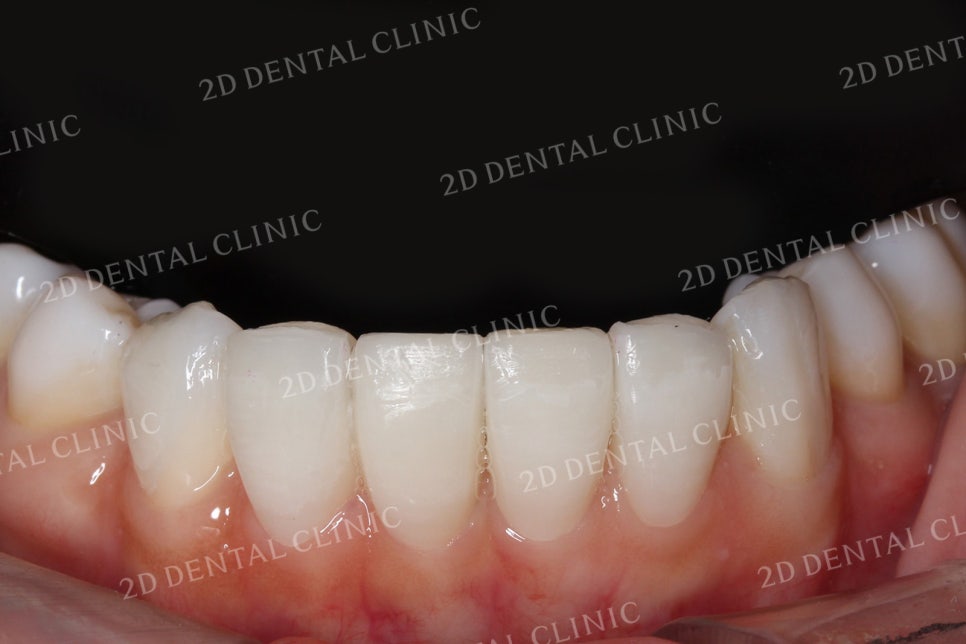

쎄라필름 시술 후

쎄라필름의 시술 전 후 사진입니다.

전치부에서 블랙트라이앵글이 발견되었던

시술 전 상태에서 시술 후 깔끔하게

치아 사이의 틈새가 사라진 모습입니다.

상하악 교합 시 사진입니다.

쎄라필름은 치아 사이의 틈새는 물론,

누렇게 착색된 치아의 색상과

일정하지 않은 형태와 크기 등을

환자분이 원하시는 방향으로

시술하실 수 있습니다.

치간이개가 특히 심하게 진행되었던

하악 전치부에서도

벌어진 틈새가 통통하고 꽉 찬

형태의 치아로 변한 모습입니다.